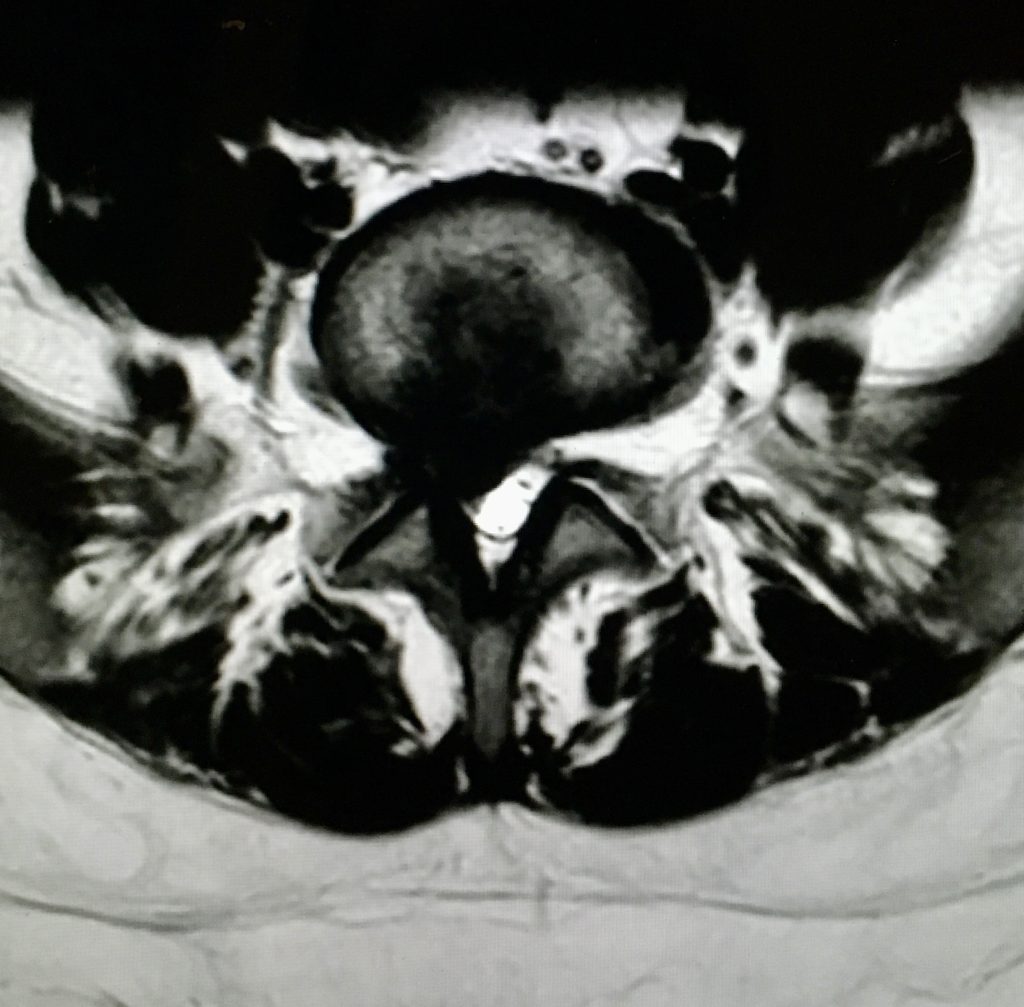

Cuando hablamos de hernia discal lumbar nos referimos a un fragmento de disco intervertebral, que extruido a través de una rotura del anillo discal, comprime una raíz nerviosa lumbar, provocando con su irritación dolor radicular tipo ciático. La cirugía consiste precisamente en la retirada de este fragmento discal del canal, consiguiendo de ese modo liberar la raíz nerviosa atrapada y el alivio de los síntomas. La cirugía realiza de forma mínimamente invasiva, ya sea utilizando el microscopio (microdiscectomía), o empleando técnicas aún menos invasivas como la endoscopia de columna.

En esta cirugía se extrae del canal espinal el material discal que está comprimiendo la raíz nerviosa. Una microdiscectomía se realiza mediante una pequeña incisión (de 3 a 4 cm) en la línea media de la espalda. La cirugía endoscopia utiliza incisiones de menos de 1 cm, lo que permite acortar los tiempos de recuperación y baja laboral. En determinados casos seleccionados, la discoplastia lumbar con sonda láser se realiza mediante la punción del disco, sin realizar herida quirúrgica.